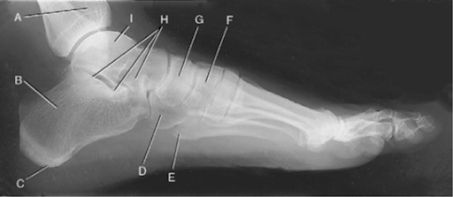

A. Articulación interfalángica del primer dedo del

pie derecho.

B. Falange proximal del primer dedo del pie derecho.

C. Articulación metatarsofalángica (MTF) del primer

dedo del pie

derecho.

D. Cabeza del primer metatarsiano.

E. Cuerpo del primer metatarsiano.

F. Base del primer metatarsiano.

G. Segundo cuneiforme o intermedio (superpuesto

parcialmente al

primer cuneiforme o interno).

H. Escafoides.

I. Astrágalo.

J. Tuberosidad del calcáneo.

K. Tercer cuneiforme o externo.

L. Cuboides.

M. Tuberosidad de la base del quinto metatarsiano.

N. Articulación metatarsofalángica (MTF) del quinto

O. Falange proximal del quinto dedo del pie derecho.